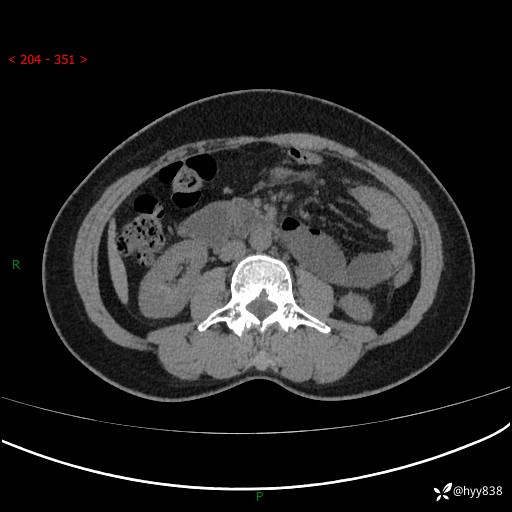

上腹部CT平扫